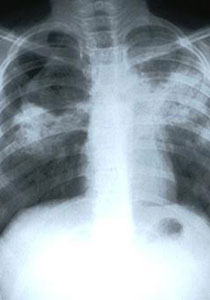

قالت "هيلين دونوجو" من جامعة كوليدج أن أقدم سلالة من مرض السل تم التعرف عليها قبل ذلك كانت في مجموعة من المصريين يرجع تاريخهم إلى 3000 عام قبل الميلاد. والسل مرض بكتيري معد يصيب في العادة الرئتين وهو يصيب الآن 2.9 مليون شخص كل عام ويقتل ما يقدر بنحو 1.7 مليون شخص في أنحاء العالم.